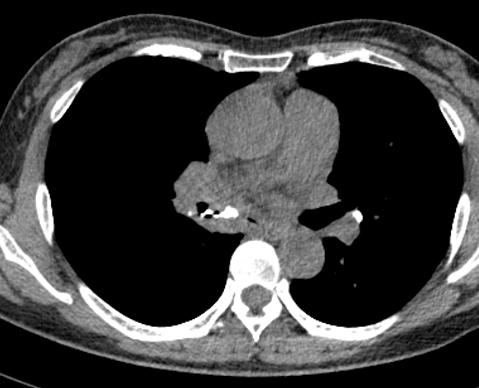

图1~图7 胸部CT示双肺多发钙化

问题在哪儿?

肺部钙化灶脱落,掉进左主支气管(图8),因为钙化病灶是坚硬的、锐利的,就像一个石头在不断地刺激支气管粘膜,导致患者咳嗽。

图8 胸部CT